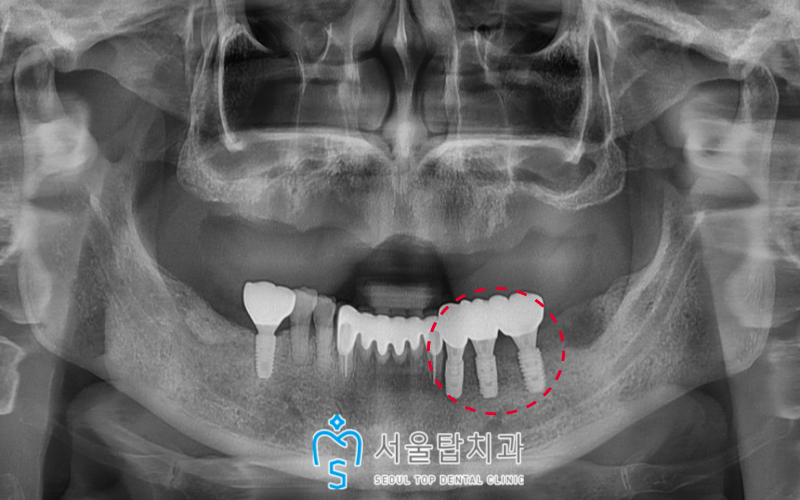

서울탑치과 임플란트

위턱 잇몸뼈가 아무는 동안

왼쪽 아래턱 임플란트 보철물을

먼저 완성시켜

불편감을 조금이나마 줄여드렸습니다.

그리고 위턱에도

발치 후 3개월이 지난 후

임플란트 수술을 시행하였답니다.

위턱 양측 어금니 부위에는

상악동 거상술을 동반하여 뼈이식을,

앞니 주변에도 잔존골이 부족하여

치조골 이식을 한 뒤

치유 기간을 충분히 가진 후

임플란트를 식립하였답니다.